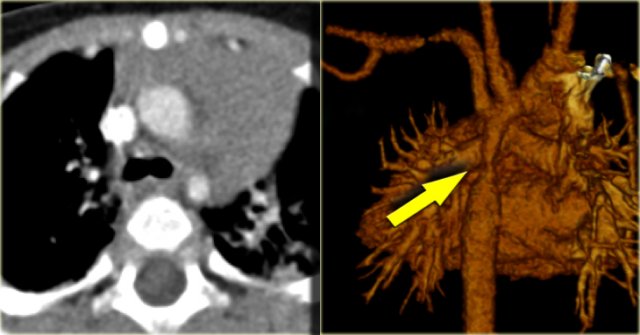

First study the axial image followed by the sagittal reconstruction, then continue.

The findings are:

• Big internal mammarian arteries on the axial image due to a high grade stenosis as a result of a coarctation. Probably could not make the diagnosis based on the axial images alone.

• Post-ductal coartation only seen on sagittal reconstruction.

• Intercostal collaterals.

Intercostal collaterals in aortic coarctation Intercostal collaterals in aortic coarctation

The intercostal collaterals typically occur between the 3rd and the 8th rib.